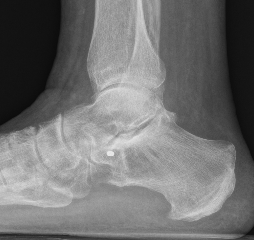

Subluxation of TNJ with advanced STJ OA

TNJ OA with posterior / medial / anterior facet OA of the subtalar joint